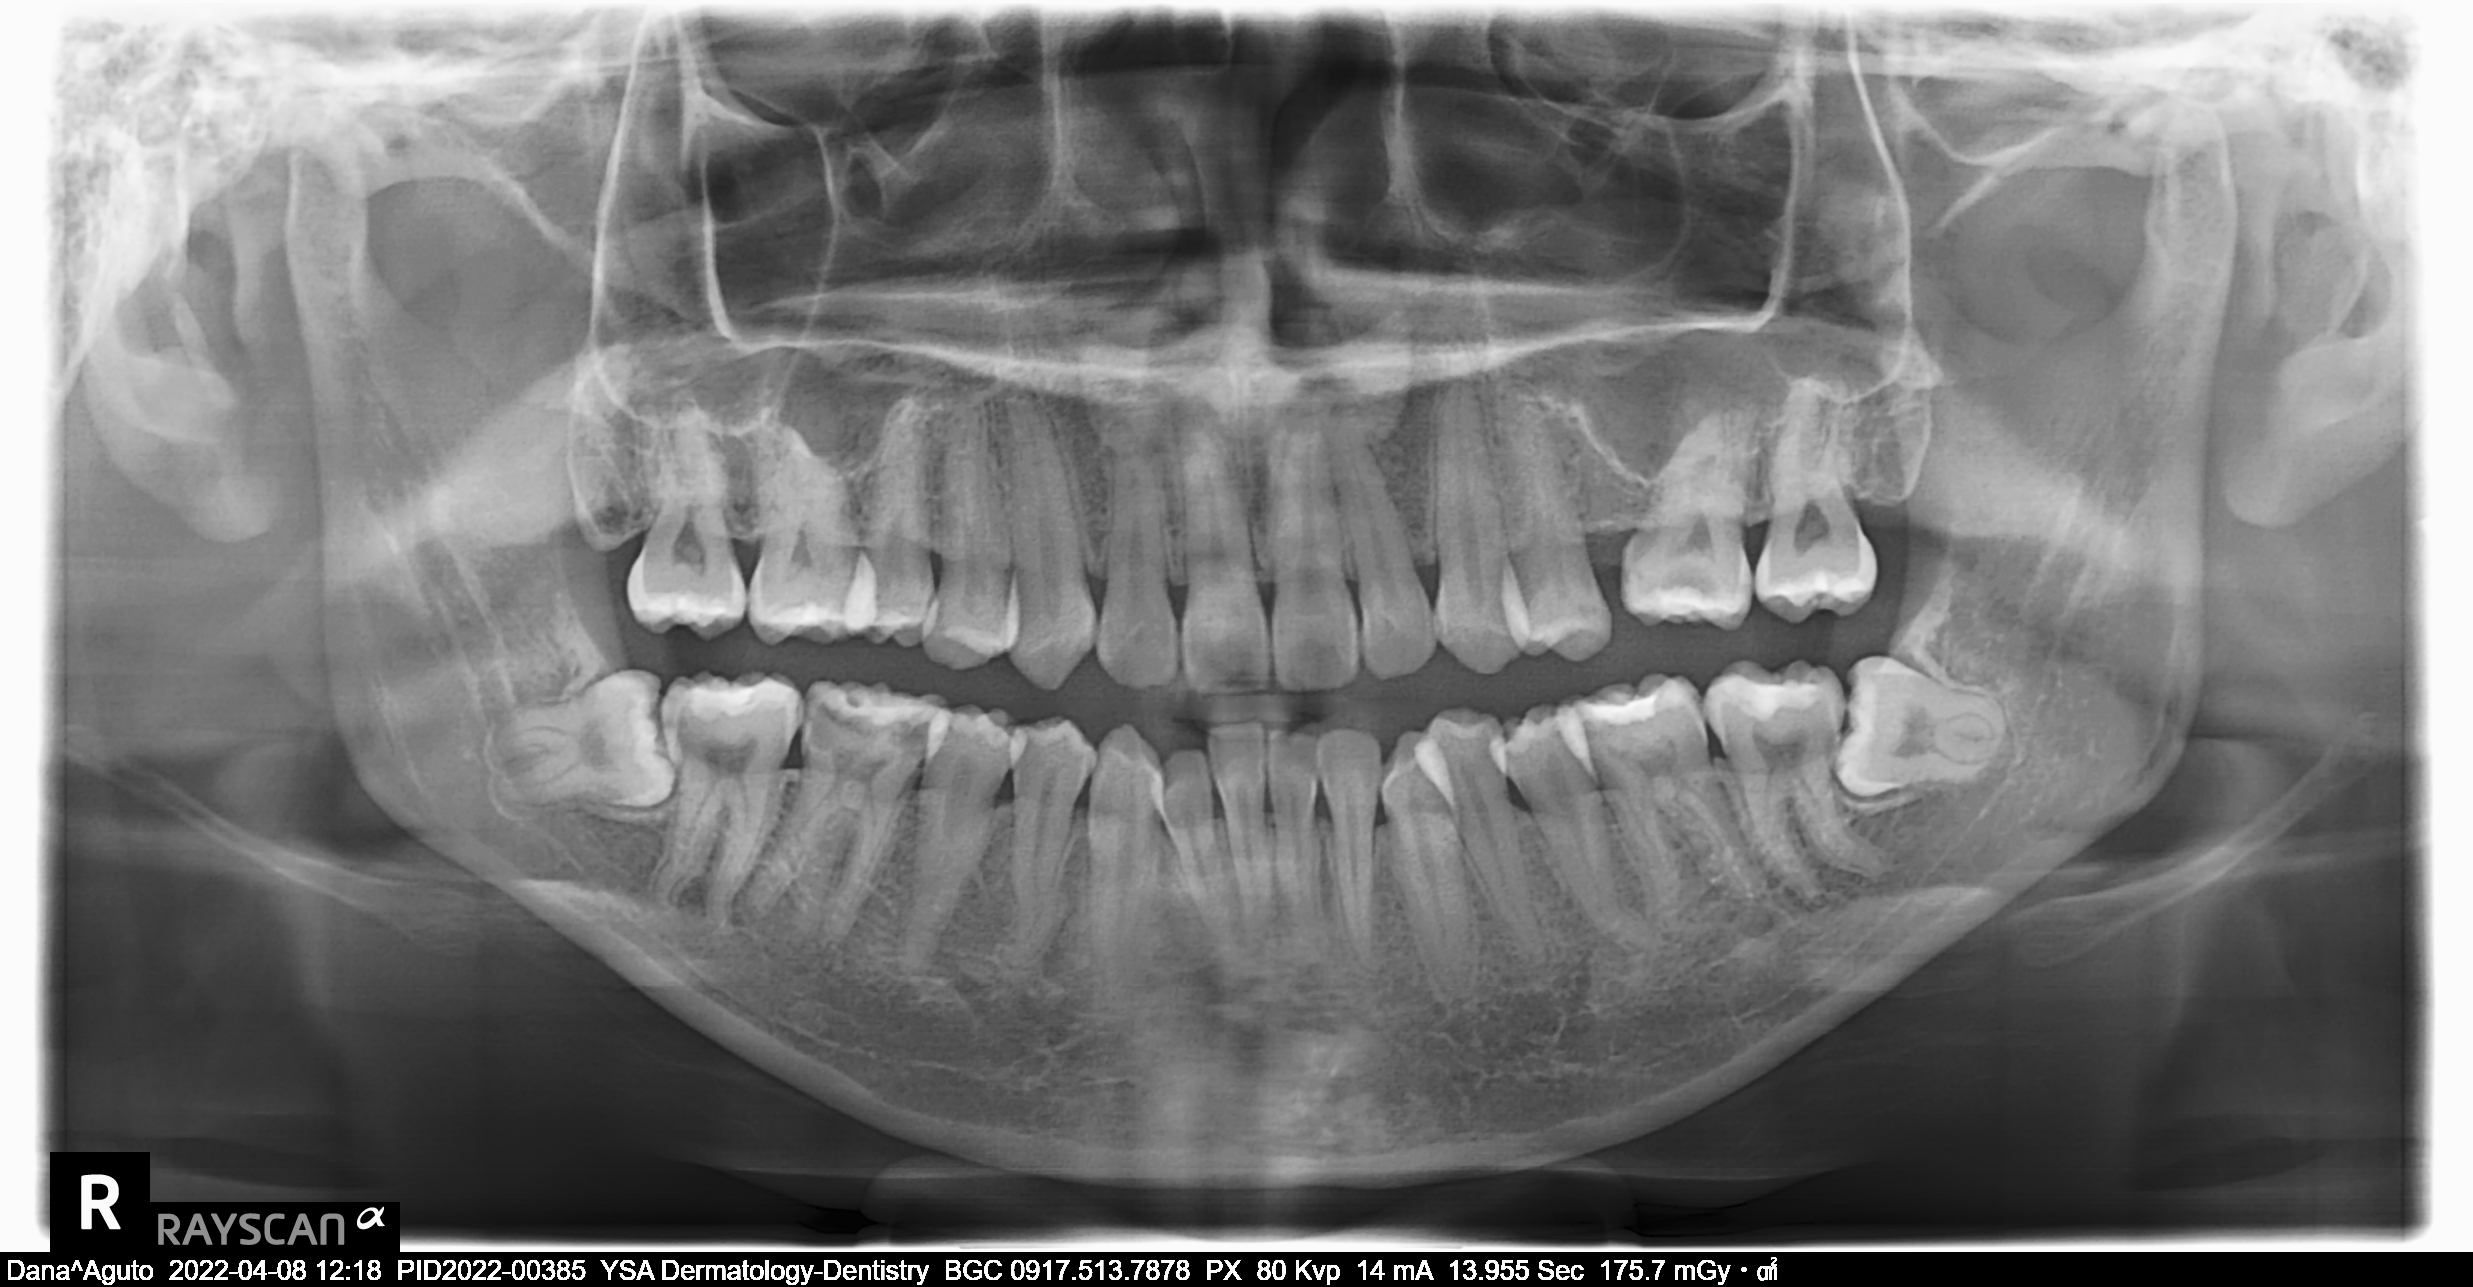

Edit Record Check our patient data records. Add patient information Patient Info Profile picture Last Name First Name Middle Name Birthdate Age Street Barangay City Country Zip Code Contact number Email Procedure 4/8/22- check up ***pano/ ceph ***#46 exo presence of lip tie 04/02/22 odontectomy 48/38- class 3/ mesioverted exo 46/ tongue tie/ ankyglossia frenectomy (laser) pt under IV CS Ozone therapy ****ff up after 2 weeks/ ***for orthodontic treatment 06/16/22 LC 24 OD/ CAOH LC 47 M op/ OZONE 1/11/23- Adj , 16niti Upper, Rotational Wedge # 42D , reattached #35 11/04/22-OP/LC 15,36,26,/mta/XRAY 11/16/22-InsOfBraces/Niti 14/14(MBT0.22) 12/07/22-adj 01/11/23- adj 04/12/23- same wire U/ Lower NiTi 16/ reattached #34,15/IPR between #32-33 05/05/23- U same wire; L SS-16; Resto #14DO, #15MOD, #16D 06/07/23- Informed Consent Resto #14DO (redo) Ortho UL same wire Remove RW #33 Monkey elastics #13-#23-#33-#43 07/19/23- Lc 36 occusal, lingual 18 ss U 18ss l rw 33 distal 08/18/23- 09/15/23- same wire #22 extrude 10/13/23 - adjustment, same wire - RW on #12 mesial 12/13/23-16X16 L -Penguin Cross Elastic -Upper to Right -Lower to left 01/12/24- adjustment same wires X-elastics on posterior Pms FOR removal on APRIL 02/21/24 same wire chain upper and lower rabbit to 3's to 4's 03/22/24 same wire rabbit 43 to 25 chipmunk 13 to 45 RW #45 distal 04/19/24 Removal of braces for retainers( vacuumed retainers) OP w/ flouride impression U/L 07/19/25 op with air polisher 03/18/26 Summer smile promo LC #14 - M,O, D + caoH + GI #15 - M,O,D + desen #16- M, O, Li + caoH + GI 03/26/26 Redo 04/08/26 check up 05/14/26 LC #16- fiber + mta File dana46.jpg File 2 file_0001_1_2.jpg File 3 file_0001_3.jpg File 4 dana_aguto.jpg File 5 dana_aguto_02.jpg File 6 dana_aguto_03.jpg File 7 dana_guto_04.jpg File 8 img_20240406_103512.jpg File 9 File 10 File 11 File 12 File 13 File 14 File 15 File 16 File 17 File 18 File 19 File 20 Retain Record Retain Record Yes No Save Your Changes